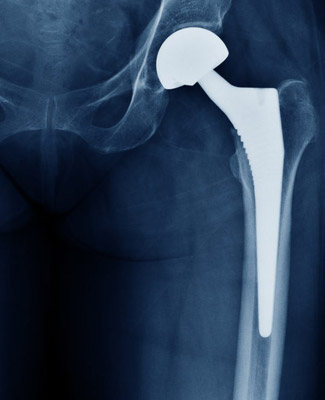

Orthopedic Digital X-Ray Systems play a critical role in diagnosing orthopedic injuries such as fractures, muscle strains, and torn tendons or ligaments that can severely limit mobility and quality of life. Understanding the recovery process is essential to restoring health and function. KnovelTech empowers orthopedic practices with advanced diagnostic imaging solutions that deliver clear, accurate, and efficient results, helping physicians identify injuries quickly and guide patients toward faster recovery

At KnovelTech, we understand that accurate diagnostics are the foundation of effective orthopedic treatment, and our Orthopedic Digital X-Ray Systems are designed to support the full continuum of care—from initial injury assessment to ongoing recovery. By combining cutting-edge technology with user-friendly design, KnovelTech helps orthopedic professionals restore their patients’ mobility, confidence, and quality of life